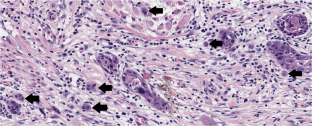

Almangush, A., Mäkitie, A.A. & Leivo, I. Tumour budding in head and neck cancer: what have we learnt and the next steps towards clinical implementation. Br J Cancer 130, 1–2 (2024). https://doi.org/10.1038/s41416-023-02531-4